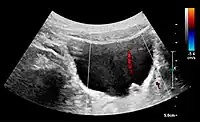

Figure 5. Simple renal cyst with posterior enhancement in an adult kidney. Measurement of kidney length on the US image is illustrated by '+' and a dashed line.[1]